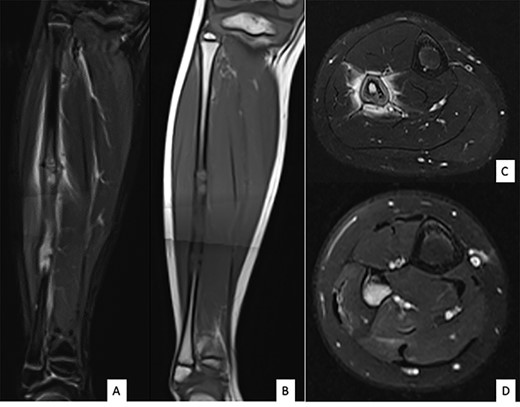

Ultrasound showed a diaphyseal subperiosteal hematoma of the fibula with cortical irregularities. The radiograph showed a pathological fracture, at the upper end of a cortical bone lesion of mixed osteolytic and osteoformative character with bone callus (Fig. 1). MRI showed a multifocal osteolytic cortical process extending along the fibular shaft, without tumor mass in the soft tissues with respect for the signal of the medullary cavity. The perilesional soft tissues were respected, but they appeared in strong hypersignal T2 and enhanced after injection of gadolinium (local inflammatory reaction or post-traumatic changes; Fig. 2).

MRI of the right fibula: coronal MR STIR imaging (A); T1-weighted imaging (B); axial T2 FAT SAT section of the proximal part (C) and distal part (D) of the lesion. MRI shows areas of osteolysis around a medullary cavity narrowed by cortical thickening (sclerosis) and diffuse tissue inflammatory edema leading to suspicion of chronic osteomyelitis.